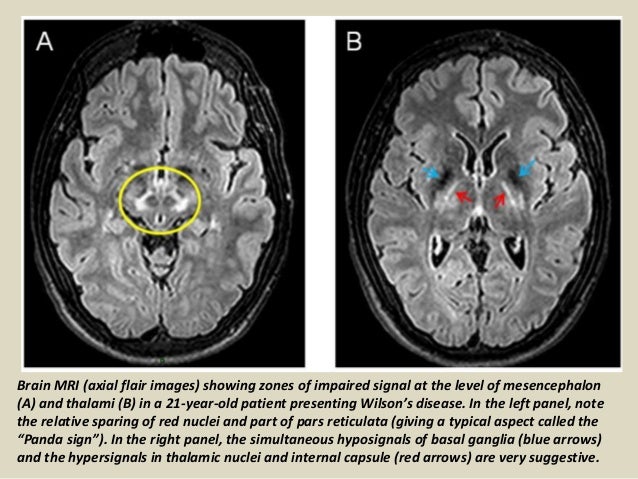

Interval changes on follow-up MR imaging were also closely correlated with clinical findings and. MRI of the brain appears to be more sensitive than CT scanning in detecting early lesions of Wilson disease. The face of the giant panda sign panda sign of the midbrain or double-panda sign is a characteristic pandas face appearance in magnetic resonance imaging MRI images of people with Wilsons disease.

1 In addition a second miniature panda face can be seen in the high signal abnormality in the pons figure C. To describe the spectrum of brain abnormalities in Wilson disease hepatolenticular degeneration as depicted at magnetic resonance MR imaging and computed tomography CT and to relate these findings to neurologic and hepatologic abnormalities.

To describe the spectrum of brain abnormalities in Wilson disease hepatolenticular degeneration as depicted at magnetic resonance MR imaging and computed tomography CT and to relate these findings to neurologic and hepatologic abnormalities. Positive findings believed secondary to this condition were found in 15 subjects. It is found worldwide with a prevalence of approximately 1 case in 30000 live births in most populations. Thirty-eight patients with biochemically proven Wilsons disease underwent magnetic resonanceimaging MRI of the brain as well as neurological examinations. Fifty patients with Wilson disease participated in the cross-sectional. The face of the giant panda sign panda sign of the midbrain or double-panda sign is a characteristic pandas face appearance in magnetic resonance imaging MRI images of people with Wilsons disease. 1 In addition a second miniature panda face can be seen in the high signal abnormality in the pons figure C.